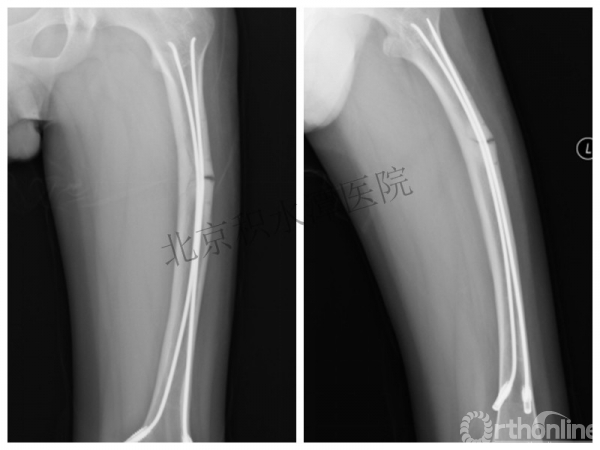

病例分享一

男孩 、5岁,初次骨折于2007年7月。

术后2年→再骨折→再次手术

钢板固定后一年

取板后再骨折→TEN

TEN取出后2个月

闭合复位再固定加尾帽

又过了4年!时间来到2015年

一年以后顺利愈合,实则危机四伏

数月后再骨折!牵引!

髋人字支具

外固定架术后一年

整整11年!是否治疗终结?